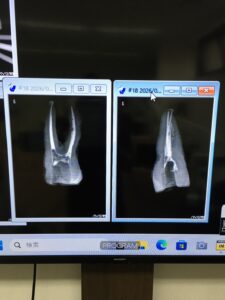

M先生

前日に二人でw水炊き屋に行ったM先生。

彼のテストケースは以下だ。

パフもあり、上手い!

先生も教わる方でなく、技術を人に伝え伝承していく側の人間だ。